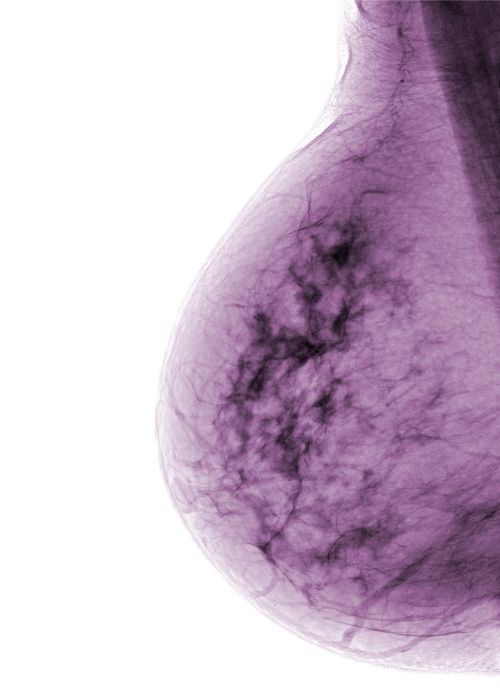

Dense breast tissue is not something you or your physician can feel. It can only be detected through a mammogram. Radiologists then differentiate breast density according to four categories (see Exhibits A-D, found in NBCF’s “Dense Breasts Q&A Guide”):

- Class C: Heterogeneously dense. The majority of the tissue is dense.

- Class D: Extremely dense. Almost all of the tissue is dense.

“Dense breast tissue could complicate a breast cancer diagnosis because both cancer and dense tissue appear as white on a mammogram,” she explained. “Fatty tissue is black. Recent research also indicates that women categorized as Class D may be at higher risk for developing breast cancer. But having dense breast tissue is not an abnormal finding, so it shouldn’t necessarily sound an alarm.”